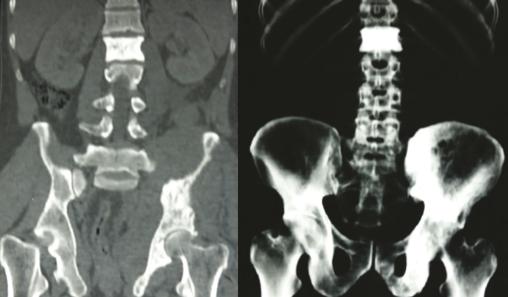

Les radiographies standards mettent en évidence une vertèbre ivoire L1 ainsi qu’une ostéocondensation de l’os iliaque gauche (fig. 1 ). Le scanner thoraco-abdomino-pelvien montre une atteinte osseuse mixte de l’aile iliaque gauche (fig. 2 ), un envahissement des parties molles (avec augmentation des volumes des muscles fessiers et du psoas [fig. 3 ] expliquant la sciatalgie), une néphromégalie unilatérale, une splénomégalie nodulaire et de multiples adénopathies abdomino-pelviennes et thoraciques.

Les radiographies standards mettent en évidence une vertèbre ivoire L1 ainsi qu’une ostéocondensation de l’os iliaque gauche (